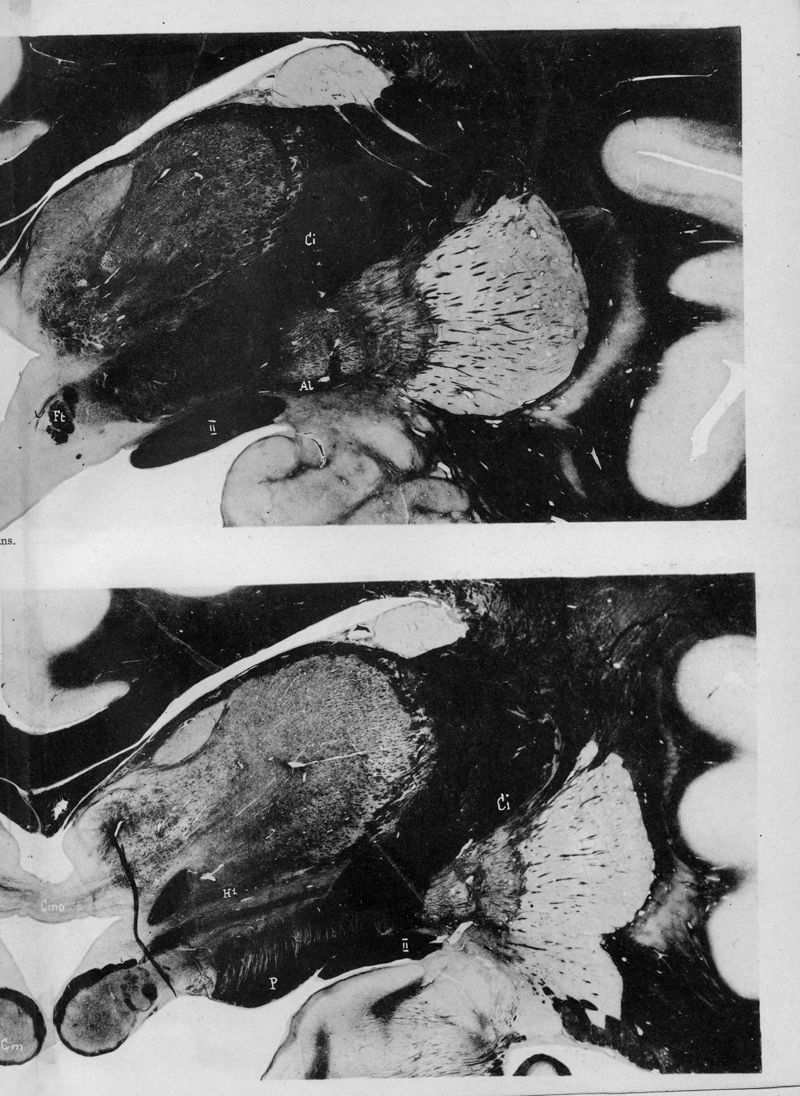

VOGT, Cécile / VOGT, O.

In : Journal für Psychologie und Neurologie,

1920, Vol. 25, pp. 627-846